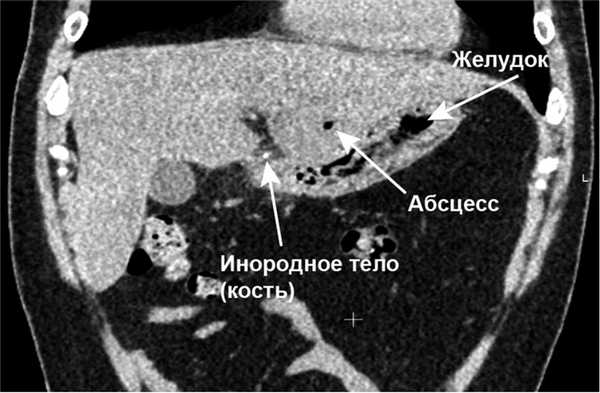

Результаты лабораторных исследований: лейкоциты (WBC) 11,7·10 9 /л; гемоглобин (HGB) 134 г/л, биохимический анализ крови — без отклонений от нормы. Начато проведение антибактериальной терапии (ципрофлоксацин 400 мг 3 раза в день в/в, метронидазол 500 мг 3 раза в день в/в). Учитывая неясный генез образования абсцесса, с целью дообследования была выполнена КТ органов брюшной полости с в/в болюсным усилением, по результатам которого выявлено инородное тело, располагающееся в передней стенке выходного отдела желудка (рис. 1, 2), размерами 30×2 мм с пенетрацией в паренхиму S3 печени и формированием абсцесса 45×35×30 мм (рис. 3, 4).

Рис. 1.ПациентП. КТоргановбрюшнойполостивнативномрежиме. Визуализируются инородное тело и абсцесс печени.

Рис. 3. Пациент П. КТ органов брюшной полости в венозную фазу, фронтальный срез. Визуализируются инородное тело и абсцесс печени.